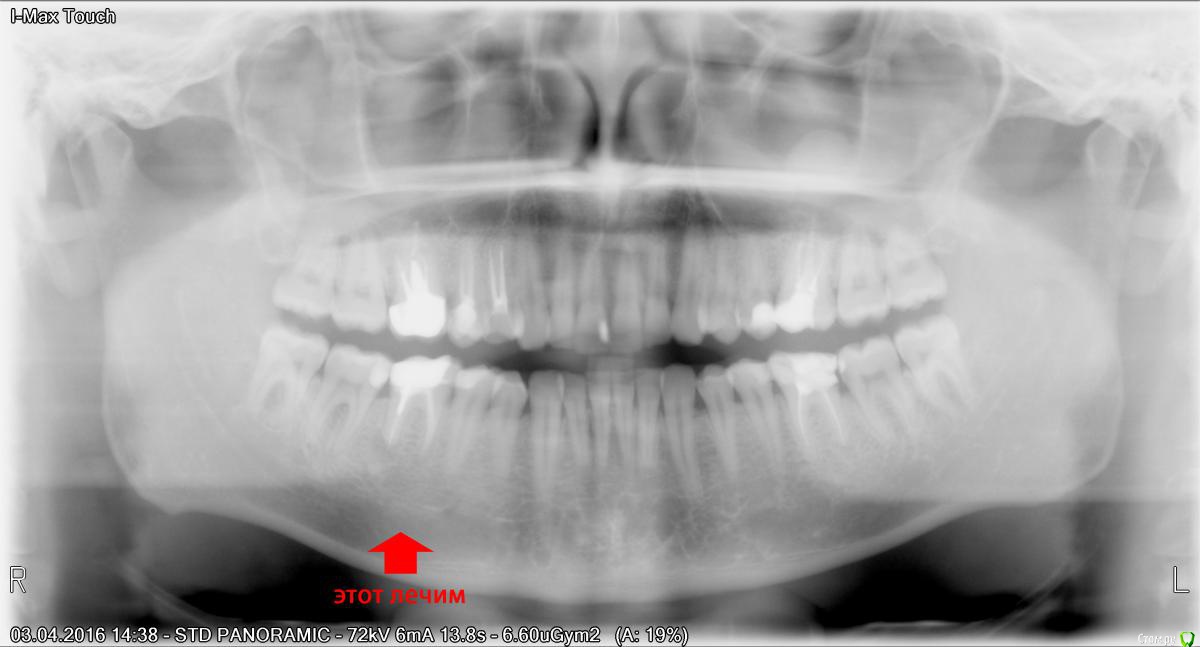

n1n1 Опубликовано 16 июля, 2016 Поделиться Опубликовано 16 июля, 2016 Снимок прилагаю. Пломба пару лет назад откололась, болей не было, Но наконец-то дошел до стоматолога, по снимку обнаружили на корне зуба кисту, положили первое лекарство, поставили временную пломбу на 10 дней. Сейчас идет 7-й день и по нарастающей болит соседний (задний) зуб. Стоматолог говорит, что хорошо бы его тоже вскрыть, но до установки лекарства он не беспокоил, поэтому с мой стороны вскрывать не хочется. Что скажите? Ссылка на комментарий